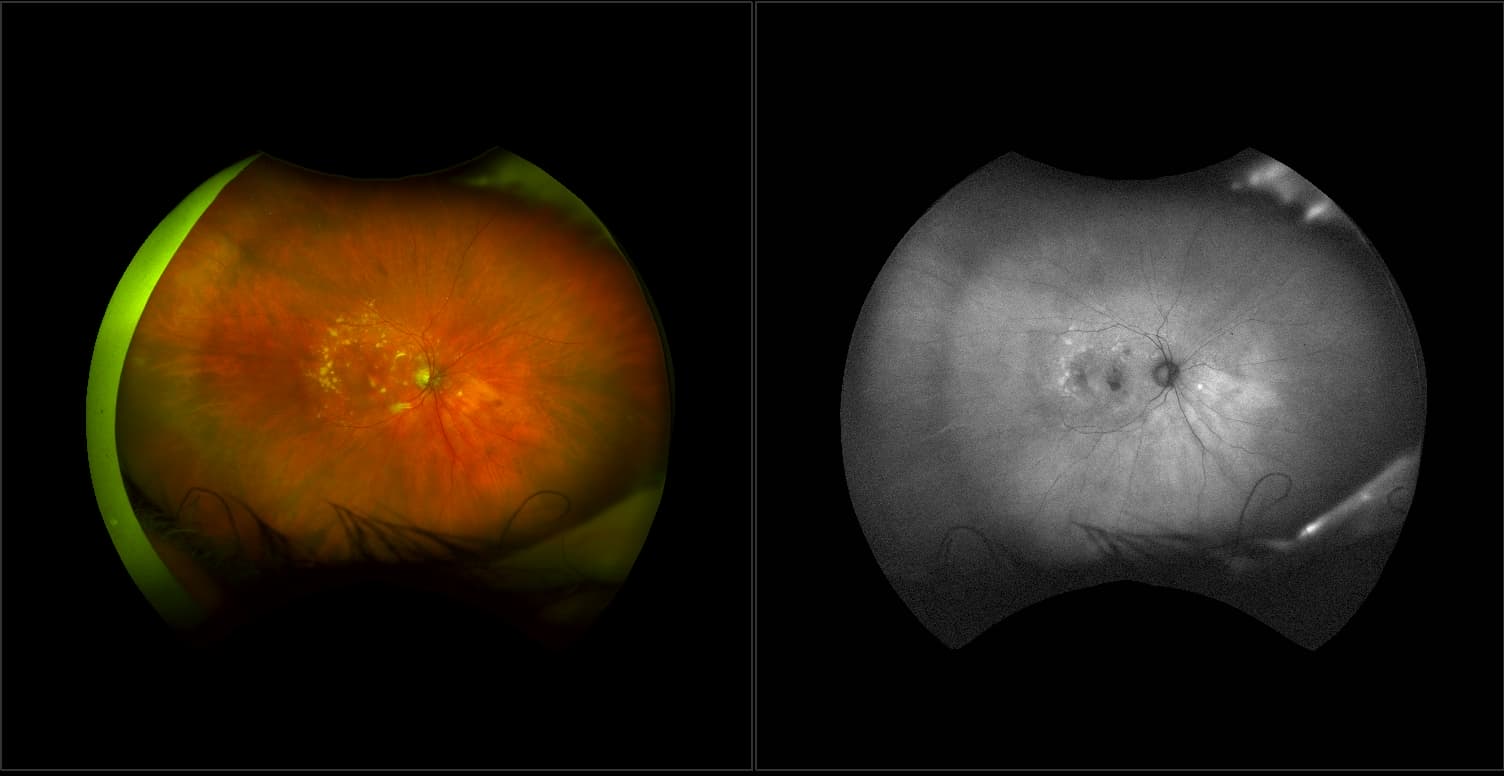

California - AMD, RG, AF

Age-related macular degeneration is found in two forms 1. Dry early form. 2. Wet (serous leakage or whole blood). Early dry form typically has drusen (usually around 63u) and RPE degeneration and only needs periodic follow-ups, intermediate dry form has large drusen (>125u) and RPE degeneration and proliferation which requires examinations every 3 to 6 months depending on the severity of the presentation.